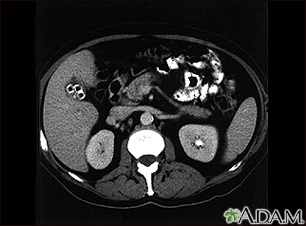

Cholecystolithiasis